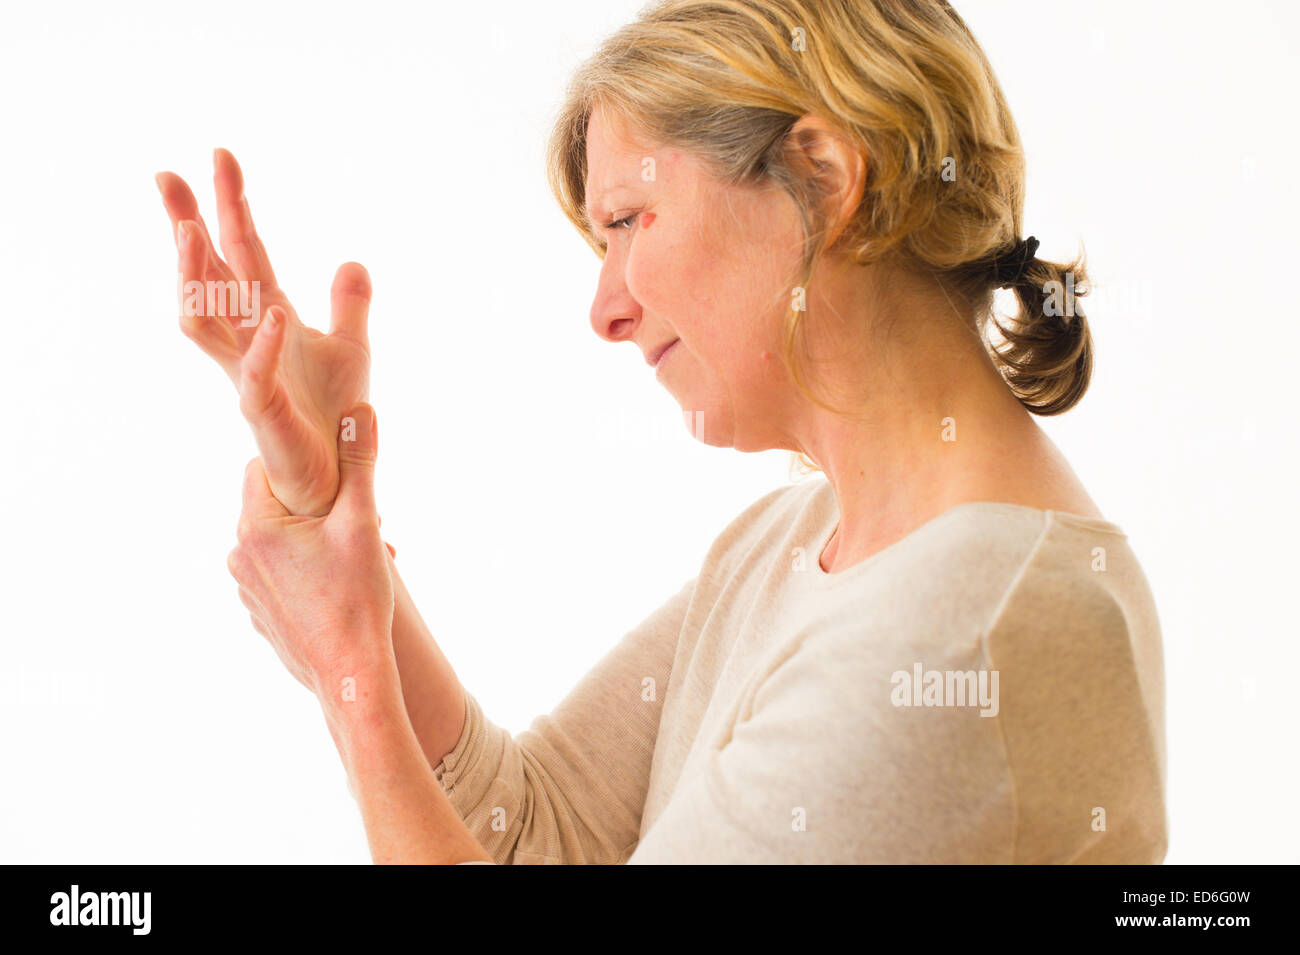

A forty year old caucasian woman with painful arthritis in the joints of her hand wrist and fingers, rubbing her wrist for pain relief, against a white background. UK Stock Photohttps://www.alamy.com/image-license-details/?v=1https://www.alamy.com/stock-photo-a-forty-year-old-caucasian-woman-with-painful-arthritis-in-the-joints-76976283.html

A forty year old caucasian woman with painful arthritis in the joints of her hand wrist and fingers, rubbing her wrist for pain relief, against a white background. UK Stock Photohttps://www.alamy.com/image-license-details/?v=1https://www.alamy.com/stock-photo-a-forty-year-old-caucasian-woman-with-painful-arthritis-in-the-joints-76976283.htmlRMED6G0Y–A forty year old caucasian woman with painful arthritis in the joints of her hand wrist and fingers, rubbing her wrist for pain relief, against a white background. UK